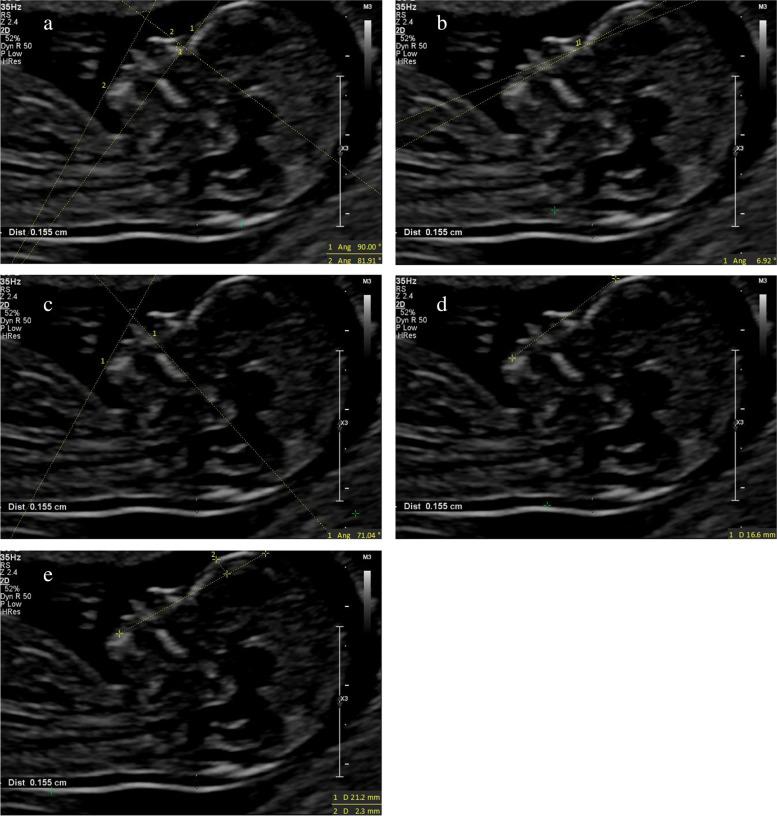

To study the correlations between facial profile markers and crown-lump length (CRL) in a Chinese population, and to evaluate the clinical value of these markers for abnormal fetuses during the first trimester (11 to 13 gestational weeks).  METHODS: The facial profile markers were as followings: inferior facial angle (IFA), maxilla-nasion-mandible (MNM) angle, facial maxillary angle (FMA), frontal space (FS) distance and profile line (PL) distance. These markers were measured in facial mid-sagittal section through ViewPoint 6 software. The diagnostic value of these markers for abnormal fetuses was assessed by receiver operating characteristic (ROC) curves.

According to the first-trimester scanning (FTS) and follow-up, 31 fetuses were enrolled in the abnormal group, including 14 cases of trisomy 21, 7 cases of trisomy 18, 10 cases with cleft lip and palate (CLP), and 1000 normal fetuses were selected. Among the normal fetuses, the IFA, FS distance and PL distance had negative correlations with CRL. The MNM angle and FMA had positive correlations with CRL. The mean IFA values for fetuses with trisomy 21 and trisomy 18 were 74.11° (standard deviation (SD) 7.48) and 69.88° (SD 7.08), respectively, which were significantly smaller than the normal fetuses (p = 0.013; p = 0.003). The mean MNM angle of fetuses with trisomy 18 and CLP were 6.98° (SD 2.61) and 9.41° (SD 2.57), respectively, which were significantly greater than the normal fetuses (p = 0.005; p < 0.001). The mean FMA values of trisomy 18 fetuses were 63.95° (SD 4.77), which was significantly smaller than the normal fetuses (p < 0.001). The mean FS distance of CLP fetuses was -0.22 mm (SD 1.38), which was significantly smaller than the normal fetuses (p < 0.001). The mean PL distance of trisomy 21, trisomy 18 and CLP fetuses were 2.89 mm (SD 0.41), 2.91 mm (SD 0.56) and 2.71 mm (SD 0.37), respectively. The difference with the normal fetuses had no statistical significance (p = 0.56; p = 0.607; p = 0.54).

面部轮廓标志如下:下面部角(IFA)、上颌-鼻根-下颌(MNM)角、面上部角(FMA)、额面间距(FS)和轮廓线(PL)距离。通过 ViewPoint 6 软件在面部正中矢状面测量这些标志。通过受试者工作特征(ROC)曲线评估这些标志对异常胎儿的诊断价值。

根据孕早期扫描(FTS)和随访,31 例胎儿被纳入异常组,包括 14 例 21 三体,7 例 18 三体,10 例唇腭裂(CLP),1000 例正常胎儿。在正常胎儿中,IFA、FS 距离和 PL 距离与 CRL 呈负相关。MNM 角和 FMA 与 CRL 呈正相关。21 三体和 18 三体胎儿的 IFA 平均值分别为 74.11°(标准差(SD)7.48)和 69.88°(SD 7.08),显著小于正常胎儿(p=0.013;p=0.003)。18 三体和 CLP 胎儿的 MNM 角平均值分别为 6.98°(SD 2.61)和 9.41°(SD 2.57),显著大于正常胎儿(p=0.005;p<0.001)。18 三体胎儿的 FMA 平均值为 63.95°(SD 4.77),显著小于正常胎儿(p<0.001)。CLP 胎儿的 FS 距离平均值为-0.22mm(SD 1.38),显著小于正常胎儿(p<0.001)。21 三体、18 三体和 CLP 胎儿的 PL 距离平均值分别为 2.89mm(SD 0.41)、2.91mm(SD 0.56)和 2.71mm(SD 0.37),与正常胎儿相比差异无统计学意义(p=0.56;p=0.607;p=0.54)。